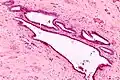

| High magnification micrograph of endosalpingiosis, showing the characteristic cystic spaces lined by a simple epithelium with cilia. H&E stain. | |

It is characterized by cysts with tubal-type epithelium (e.g. ciliated epithelium) surrounded by a fibrous stroma. It is not often associated with hemorrhage.